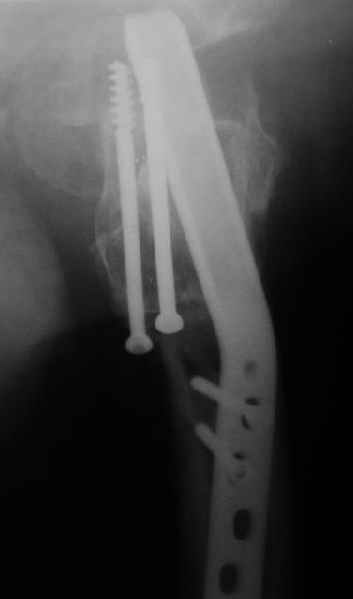

Мужчину 56 лет оперировали у нас в августе 2003 г. - вальгизируюшая остеотомия из-за позднего (через 2 мес. после травмы) поступления с переломом шейки бедра (картинки 1,2). Курильщик, соматической патологии не было. Сейчас поступил с жалобами на проблемы в области тазобедренного сустава, на снимках 3,4 видно вырезывание клинка.

A male 56 years old was operated in Aug 2003 - valgus osteotomy performed because of delayed admission with neck fracture (2 months) images 1,2. Smoker, no other major medical problem.